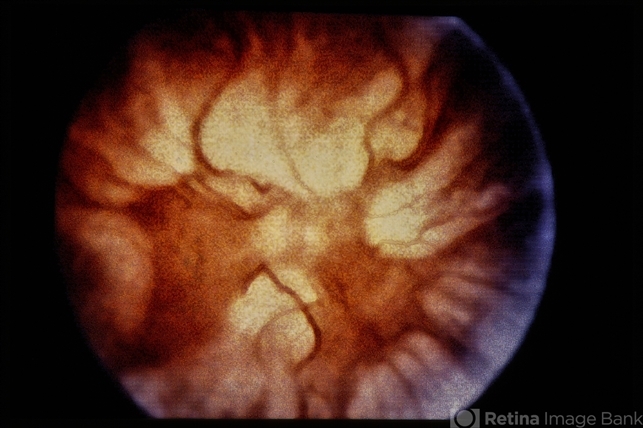

- color fundus photograph

- D3 PVR with funnel-shaped retinal detachment.